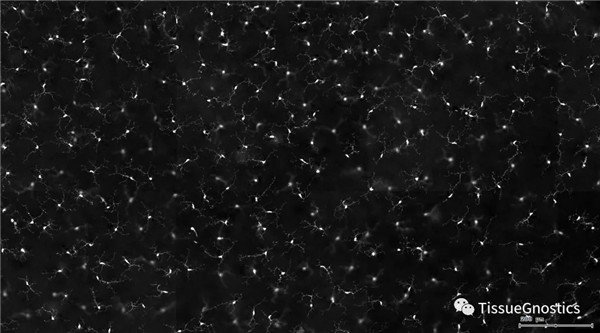

視網膜熒光樣本中小膠質細胞胞體、神經纖維識別、血管識別、血管斑點識別、神經元與血管的距離分析。

單通道灰階圖(↑:FITC,↓:Texa Red)